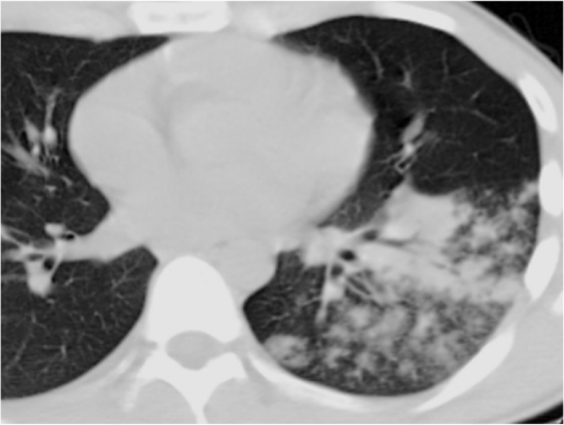

Lemierre综合征(LS)是以法国医生Andre Lemierre的名字命名,他在1936年报告了20例由口咽感染引起的厌氧败血症。(1)流行病学:在抗生素广泛应用的年代,LS的发病率急剧下降。自70年代后期口腔感染中经验性抗生素的使用减少,报告的病例数量稳步上升,被称为“被遗忘又重现的疾病”,发病率为每年1/10000000,通常为青少年和年轻人,即使使用适当的抗生素和治疗,报道死亡率也在5%~18%之间。(2)致病菌:导致LS的致病菌通常为坏死梭杆菌(>70%),它是严格的专性厌氧革兰氏阴性杆菌。(3)病理生理:首先由于细菌、病毒致咽部黏膜损伤,在此基础上出现坏死梭杆菌的二重感染:①感染至咽外侧间隙和颈部软组织,引起外源性压迫,出现炎症、水肿;②内源性闭塞,出现血管内凝血。在上述基础上发生颈内静脉脓毒性血栓形成;感染性栓子从任何一条静脉播散,都可能导致肺、胸膜、关节、骨骼、肌肉、肝、脾、肾等多处器官受累。(4)临床特征:①口咽感染;②颈内静脉血栓性静脉炎感染延伸至颈部旁间隙;③脓毒性栓子播散引起菌血症、脓毒性休克。(5)诊断:①血培养:培养时间需要6~8天,阳性率低;②分子生物学方法:快速且准确,有助于早期诊断;③BALF、m-ROSE、NGS等。LS的Sinave诊断标准:①口咽部的原发感染;②脓毒败血症;③颈内静脉感染性栓塞;④远处脏器转移性化脓灶。(6)治疗:①抗菌药物治疗:碳青霉烯类、β-内酰胺/β-内酰胺酶抑制剂联合甲硝唑是治疗LS最有效的药物。②抗凝治疗。③外科治疗。(1)定义:齿垢密螺旋体是一种螺旋形的革兰氏阴性厌氧菌,属解糖密螺旋体,与口腔以及牙周感染性疾病密切相关。(2)流行病学:关于齿垢密螺旋体,近4年来仅有寥寥数篇报道,极为罕见。(3)易患人群:长期卧床、生活无法自理导致口腔卫生较差、牙周状况不理想、免疫功能低下的老年人。(4)临床症状:多为非特异性症状,可有吸入性肺炎的一系列临床表现,如咳嗽、咳痰、甚至咯血,也可有畏寒、发热等。(6)治疗:目前仍按照密螺旋体属中常见人致病螺旋体进行治疗,首选为青霉素,其他如半合成青霉素、四环素类等药物亦有较好效果。患者男性,72岁。主诉:间断咳痰、咯血1月半余,发现肺结节1月余。患者2023年2月中旬无明显诱因出现间断咳痰,咳白黄痰,痰中带血,每天5~6次,无发热,无胸痛等不适,后出现咯鲜血,咯绿豆大小血块,4~5次/天,就诊于当地医院,胸部CT提示左肺上叶占位,予莫西沙星抗感染治疗约1周后症状好转,后就诊于我院。入科后,予患者支气管镜下肺泡灌洗并将BALF送检mNGS,结果回报检出齿垢密螺旋体(序列数36条)。予哌拉西林他唑巴坦4.5 g q8h+米诺环素100 mg q12h抗感染,调整治疗方案为美罗培南1 g q8h,后期仅采用替加环素50 mg q12h治疗。抗感染治疗后,患者左肺上叶结节明显缩小。非典型病原体是一种细胞内或细胞旁的细菌病原体,无法通过革兰氏染色和传统培养基进行识别,对β-内酰胺具有内在耐药性。2022年Microorganisms杂志发表的综述显示,在CAP病因中,非典型病原体占15%,这其中,肺炎支原体位居首位,其次是肺炎衣原体,然后是嗜肺军团菌以及鹦鹉热衣原体等。1976年夏天宾夕法尼亚州费城Bellevue-Stratford酒店举行的为期3天的美国退伍军人协会年度大会上,嗜肺军团菌感染首次被发现。(1)流行病学:既往军团菌肺炎的病死率可达10%~15%,院内感染死亡率可达25%~50%。随着喹诺酮类药物的临床应用,该病病死率有所下降。该病发病具有季节性,全年均可发生,以6~10月发病最多。(2)致病菌:军团菌肺炎的致病菌通常为嗜肺军团菌血清型1,约占90%,是一种需氧革兰氏阴性杆菌,细胞内寄生菌,双相生存周期。(3)传播途径:军团菌广泛存在于自然界中,尤其是温暖潮湿的环境,如人工冷水、天然水源、潮湿土壤等。军团菌感染多通过吸入受污染的人造水源(如淋浴、管道、空调系统等)产生的含军团菌气溶胶。(4)易患人群:>50岁、吸烟、免疫抑制(尤其是细胞免疫抑制)、合并慢性心肺疾病等。(5)影像学表现:肺部变化通常为单侧,主要局限于下叶,但也可能出现在两侧,包括肺部的上下部分;肺部的炎症变化可表现为3种类型的浸润——肺泡型、间质型和局灶型。军团菌肺炎的胸部X线片和CT最具特征的表现是不规则形状的肺组织大面积固结,靠近肋和/或水平胸膜,有空气支气管造影征象和局灶性肺泡-间质磨玻璃样混浊。

(6)临床表现:男性多见,约90%的患者体温超过38.5°C;呼吸道症状主要有咳嗽、咳痰、气促;神经肌肉系统表现为头痛、肌痛、关节痛;会出现相对缓脉,多脏器损害。(7)实验室指标:低钠血症,低磷血症,磷酸激酶、肝酶、ESR、CRP水平升高等。(8)影像学检查:军团菌肺炎的影像学表现具有多样性,其较为特征的改变是磨玻璃影间混杂边界分明的实变区。(9)病原学检测:分离培养(BALF培养阳性率最高)以及抗原抗体检测等(表1)。(10)治疗:①抗感染治疗:主要为经验性治疗,首选氟喹诺酮类抗生素。②尚未明确的治疗方式:药物联合治疗,如喹诺酮类+大环内酯类,以及糖皮质激素治疗,目前尚无指南共识推荐。③对于重症军团菌肺炎,可以联合ECMO(可以提高重症患者生存率)。患者,男,34岁,军人。主因“诊断慢性粒细胞白血病13年余,咳嗽6天,发热2天”于2022年7月16日收入血液科,后因喘憋加重于2022年9月1日转入我科。患者于2021年诊断亚临床甲减、桥本病,未治疗。既往有多次输血史。个人史及家族史无特殊。2008年诊断慢性粒细胞白血病,口服伊马替尼治疗约1年,后未规律监测。2020年4月自行口服伊马替尼治疗至2022年7月。2022年7月初在外出差期间发现身上多发出血点,2022年7月9日查血常规提示白细胞升高、血小板降低,具体报告未见,自行口服达沙替尼治疗,后出现腹泻,自行停药。2022年7月11日出现咳嗽,进行性加重,夜间无法入睡,伴少量黄色黏痰。2022年7月14日因头晕、乏力、腹泻加重,就诊于我院急诊,体温38.7°C,完善血常规、生化、凝血、感染指标、胸部CT,考虑为慢性粒细胞白血病加速期、肺部感染、电解质紊乱、凝血功能异常。2022年7月16日收入我院血液科。入院后相关检查显示:BALF细胞分类中性粒细胞占18%,细胞总数0.36×106。BALF GM试验1.146 μg/L。BALF及肺组织mNGS均回报嗜肺军团菌。经过抗感染治疗,患者病情好转。鹦鹉热是一种人畜共患传染病。鹦鹉热衣原体是一种专性真核细胞寄生、具有独特的发育周期、革兰氏阴性的病原菌。(1)流行病学:一年四季均可发病,秋冬季发病率升高。(2)易患人群:主要发生于中老年人群,男性多于女性,50%以上有鸟类或家禽接触史。(4)诊断:①影像学检查(胸部X线片、胸部CT)最常见的表现为肺叶变化,常合并支气管充气征等。②动脉血气分析。③BALF NGS可以明确诊断。(5)治疗:首选治疗方案为四环素类药物,包括盐酸四环素、多西环素、米诺环素。妊娠期或儿童患者可以使用大环内酯类抗生素治疗,如阿奇霉素和红霉素,疗程为7天。患者女,51岁。主诉:发热6天,咳嗽、憋喘4天,于2019年11月27日入院。既往体健,近3个月经量增多,当地诊断子宫肌瘤、黏膜下肌瘤,宫颈病变。入我院1周前发现贫血予输血。体检示右肾囊肿。家族史:父母已故。家中养3只鸡。患者于2019年11月21日无明显诱因出现发热,多于午后出现,波动在38.3°左右,就诊于当地医院。次日完善胸片示肺部感染,予哌拉西林他唑巴坦、氨曲南抗感染治疗(具体不详)。2019年11月23日出现憋喘、咳嗽,活动后憋喘明显加重,咳嗽为刺激性干咳,无咳痰。上述症状影响患者的工作及生活。患者因憋喘进行性加重于2019年11月26日转入我院急诊科,胸部CT:双肺感染性病变,右肺为著;双侧胸腔积液。急诊给予头孢哌酮舒巴坦3 g bid静滴等治疗。为进一步检查及治疗,以“肺部感染"收入我科。入院后予行气管镜检查,BALF和血NGS均检出鹦鹉热衣原体序列【对于无法耐受气管镜检查的重症患者,血NGS也是重要的诊断参考】。经过积极的抗感染治疗,患者病情得到缓解,肺部病变吸收明显。惠普尔养障体是一种杆状的革兰氏阳性细菌,可以引起全身性感染性疾病。肠道是惠普尔养障体唯一已知的天然生态位。目前该细菌已经广泛发现在各种样本中,包括BALF、唾液、尿液、血液、粪便、淋巴结等。惠普尔养障体可以从口腔菌群中吸入,导致社区获得性和吸入性肺炎,严重者可能发生呼吸衰竭甚至死亡。(1)流行病学:惠普尔养障体感染所致疾病常见于高加索人种,在亚洲和非洲人群中非常罕见。其发病率约为百万分之一。(2)易感人群:HIV阳性患者、下水道工人、流浪汉等。易感人群细菌携带率以及载量显著高于普通人。近年来由于对惠普尔养障体肺炎认识程度的提高以及诊断技术的改进,病例报告的数量也在不断增加。因此该病的实际发生率高于预期。(3)宿主:普遍认为惠普尔养障体没有重要的非人类宿主。(4)临床表现:惠普尔养障体感染所致肺炎具有广泛的非特异性临床表现。疾病早期的患者可能会出现感染、发热、关节炎和关节痛的症状;疾病中期出现腹泻、吸收不良和体重减轻等综合症状;疾病晚期则可能累及各个生理系统,在80%~90%的病例中,第一个前驱体征是关节炎和/或关节痛。入院患者则多以呼吸急促和咳嗽为主诉。(5)实验室检查及影像学:贫血、低白蛋白血症及ESR或CRP水平升高,胸部CT可能出现多种改变,包括磨玻璃影、肺结节、胸膜增厚和渗出性病变依据与肺脓肿非常相似的气液平等。(6)诊断方法:常规实验室检查常出现非特异性结果,既往最常见的诊断方法是组织病理学和PCR。近年来BALF mNGS已被证明能够提供更全面的气道细菌感染情况,识别并筛查诱发肺炎的惠普尔养障体。(7)治疗:目前推荐的治疗方案包括:头孢曲松(2 g qd) 或美罗培南(1 g tid),持续14天,后续口服复方磺胺甲噁唑(TMP-SMZ)2个月。若治疗过程中患者表现出对TMP-SMZ不耐受,则可使用多西环素。肺孢子菌肺炎是由卡氏肺孢子菌引起的呼吸系统感染,是一种发生于免疫功能受损个体中的感染,可能会危及患者生命。(1)流行病学:2012—2022年肺孢子菌肺炎发病率从2.2/10万增加至3.9/10万,30天死亡率为18.2%。(2)易感人群:HIV阳性患者,血液病,实体器官移植患者。(3)临床表现:具有非特异性。患者有进行性呼吸困难、低热等表现。(4)影像学表现:双侧弥漫性间质浸润;伴有弥漫性斑片状实变和磨玻璃影。(5)诊断:①乳酸脱氢酶(LDH)水平增加常作为HIV感染者中疑诊肺孢子菌肺炎的临床标志。②1,3-β-D-葡聚糖水平升高时,也应怀疑肺孢子菌肺炎。③DFA、qPCR检测。(6)治疗:①首选TMP-SMX治疗,剂量为15~20 mg/(kg·d),分3次或4次给药。治疗持续时间一般为21天。目前临床也有采取TMP-SMX联合卡泊芬净治疗。②辅助治疗:动脉血气显示PaO2<70 mmHg或低氧血症,建议给予糖皮质激素辅助治疗。患者男,80岁。主诉:呼吸困难4天,发热1天。于2021年2月5日入呼吸科。2020年11月发现重症肌无力(TA型),在我院神经内科住院,接受溴吡斯的明和甲泼尼龙治疗(最大剂量11片/天,规律减至4片/天)。入院后相关检查:WBC 7.31×109/L,CRP 14.2 mg/L,IL-6 394.3 pg/ml。BALF分类计数:巨噬细胞56%,中性粒细胞32%,淋巴细胞12%,嗜酸性粒细胞0。G试验355 pg/ml。床旁ROSE发现肺孢子菌包囊,NGS测序结果亦提示耶氏肺孢子菌。毛霉病是由广泛存在于自然界中的毛霉目菌属导致的感染,感染肺部多为急进性感染,可蔓延至相邻结构或血行播散至其他器官。(1)流行病学:全球发病率为1.2/10万,印度发病率为14/10万,是全球发病率的14倍。全球死亡率为57%。(2)易感人群:主要为免疫抑制患者,如流感、新冠病毒感染、糖尿病、器官移植患者等。(3)临床症状:具有非特异性。常伴有典型的肺炎表现伴咯血。(4)影像学表现:①局灶性实变、肿块、胸腔积液、多发性结节;②晕轮征提示血管侵入性真菌感染;③反晕征在毛霉菌患者中较其他侵袭性霉菌感染更常见。④伴或不伴空气新月征的空洞病灶在新冠病毒感染后毛霉病中更常见。(5)诊断:为尽快确诊,应在适当的临床情况中早期考虑毛霉病,并积极完善侵入性检查,通过组织病理学识别出具有毛霉目典型结构的微生物可能是感染的唯一证据。PCR检测可能有助于识别致病菌种。(1)流行病学:2022年年中,34个国家报告了28.8万例马尔尼菲篮状菌病例,东南亚及中国南方地区(广东、广西、福建、云南)多见。马尔尼菲篮状菌为双相型真菌,在25°C时为霉菌形态,在37°C时为酵母菌形态。(3)传播途径:尚不明确,空气传播、直接接种可产生。(4)易感人群:HIV阳性患者(89.9%),以及其他免疫受损患者(10.1%)。(5)临床表现:约70%的马尔尼菲篮状菌感染患者会出现皮肤损伤,面部、胸部、四肢随丘疹中心坏死,呈现脐状丘疹外观。(6)影像学表现:具有非特异性。可有磨玻璃改变、间质性浸润、肺大疱、空洞。(7)治疗:①诱导治疗:中重度患者(多器官受累),可选用两性霉素B治疗2周;轻度患者(仅有皮肤损伤),可选用伊曲康唑治疗。②巩固治疗:对于任意患者,建议选用伊曲康唑进行10周巩固治疗。③维持治疗:对于免疫受损患者,建议继续维持治疗,伏立康唑可作为替代用药。诺卡菌是一类有菌丝、无动力的需氧革兰氏阳性菌,在人类中可造成局部或全身性疾病,广泛存在于土壤、空气、污水和腐生物中。(1)传播途径:多通过吸入受污染的粉尘感染,可传播至呼吸道或消化道,形成局部或经血行播散至脑、肝、肾等部位。(2)易感人群:免疫功能受损患者(HIV感染、器官移植后慢性基础性肺病等)。(4)影像学特征:多见单侧/双侧肺结节,也可见肺实变、肿块、胸腔积液、网状结节。(5)诊断:根据患者的临床表现(易感因素、临床症状、CT表现)以及检查检验结果(M-ROSE、组织病理学、微生物学)进行判断。(6)治疗:抗诺卡菌治疗,重建免疫功能,降低病死率。首选TMP-SMX,15 mg/(kg·d),静脉注射。备选方案:亚胺培南西司他丁500 mg静脉注射q6h+阿米卡星7.5 mg静脉注射q12h,3~4周,改为TMP-SMX口服。推荐疗程为3个月,长期使用免疫抑制者疗程为6个月。属于机会性病原体,见于免疫功能低下、免疫缺陷患者以及婴幼儿,引发肺弓形虫病。(1)流行病学:全球输血患者患病率可达33%,接受干细胞移植患者死亡率可达43.5%。(2)致病菌:刚地弓形虫,分为强毒株RH株、弱毒株Beverley株。(3)传播途径:人畜共患。摄入生肉或熟肉中的囊肿;受感染猫科动物粪便污染基质中的卵囊;速殖子的先天性传播;输血传播。(4)临床特征:免疫功能低下患者症状明显;非特异性呼吸道症状,如发热、呕吐、腹泻、皮疹等;肺外器官受累,包括肝脾肿大、颌下及颈后淋巴结肿大等。(5)诊断:①病原学检查(确诊)。涂片染色,如姬氏染色,阳性率低,易漏检;动物接种分离法,培养7天,阴性传代3次以上。②血清学实验(辅助诊断),包括染色试验、间接血凝试验、间接免疫荧光抗体试验、PCR及DNA探针。(6)治疗:在弓形虫增殖阶段,使用TMP-SMZ,联合乙胺嘧啶可增加疗效。孕妇感染首选螺旋霉素,佐用免疫增强剂。炭疽杆菌属于厌氧、革兰氏阳性、形成孢子、非运动的、杆状芽孢杆菌,外界环境抵抗力强,导致人畜共患疾病。(1)流行病学:吸入型炭疽病死亡率为85%,摄入型炭疽病死亡率为74%。皮肤型炭疽病死亡率为46%,注射型炭疽病死亡率为33%。(2)致病菌:炭疽杆菌,分为生物活性的植物形态和生物惰性的孢子形态。(3)传播途径:人畜共患。接触濒死或已死亡动物(屠宰动物);接触受污染的动物产品(皮革、骨粉肥料);食用受污染的肉类;自注射(注射受污染的毒品);院内传播。(4)临床表现:①吸入性炭疽:潜伏期1~7天;初始阶段轻度发热、疲劳、排痰性咳嗽和胸痛或腹痛。严重阶段则为高热,毒血症、呼吸困难和发绀,甚至休克、死亡。纵隔增宽是吸入性炭疽的典型表现。②胃肠道炭疽:潜伏期3~7天,病变可见于胃肠道的任何一点,发热、咽痛、吞咽困难、恶心、呕吐、厌食、腹泻等。可从血液、腹水和病变组织中分离出炭疽杆菌来明确诊断。③皮肤炭疽:潜伏期2~7天;最初可为瘙痒性皮疹,可逐渐进展为红斑和水肿包围的水疱,最后有焦痂形成。④注射性炭疽:是炭疽病的一种新型临床形式,软组织在注射部位被感染并导致毒血症和败血症。(5)诊断:炭疽病的诊断组结合患者的基本情况和临床检查检验综合判断。基本情况包括患者的病史、症状、体征、旅居史、动物接触史等。临床检验检查包括血培养(金标准)、PCR、影像学(纵隔增宽、胸腔积液和实质浸润等)、BALF或活检标本等。